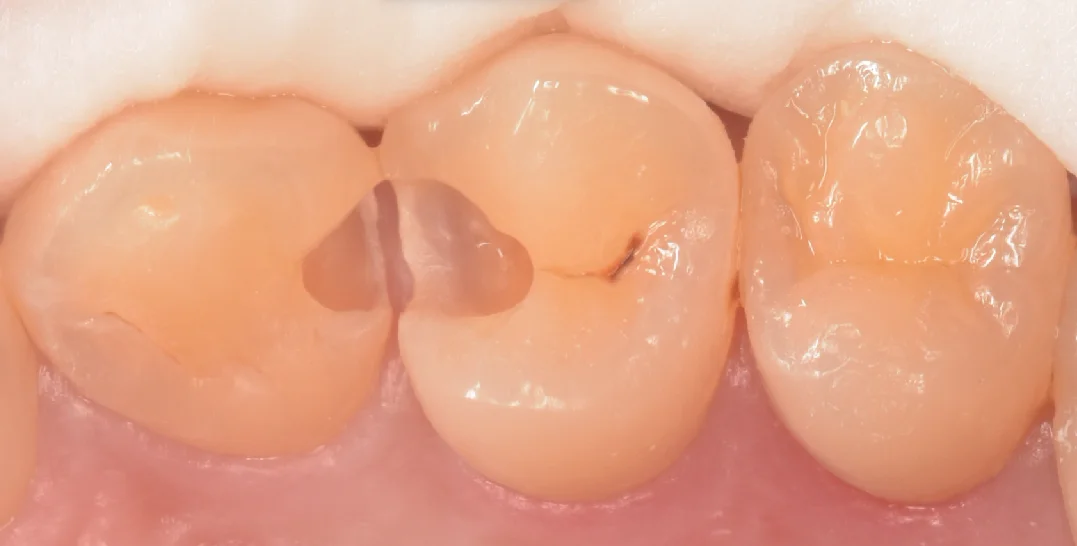

さて、虫歯を取り切ったのがこちらになります。

綺麗な歯の色が出たのがわかると思います。

こう言った歯との間の治療を行う際に私が意識していることの1つに、「歯茎側のエナメル質はなるべく残す」というのがあります。

これは接着修復に携わる歯科医師ならほぼ全員知っていることではありますが、歯の最表層に存在するエナメル質と歯の内部に存在している象牙質は接着力が大きく違います。

エナメル質の方が圧倒的に接着力が強く、また後々の加水分解も起こってこないため、この部分にエナメル質が残存しているかどうかは長期予後を得られるかどうかに大きな影響があると私は考えているからです。